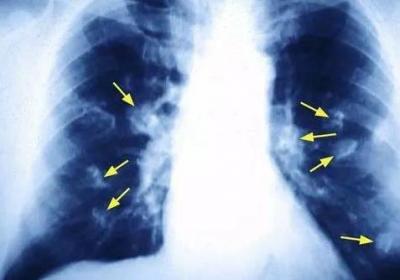

揪出引發(fā)女性肺癌的罪魁禍?zhǔn)?廚房油煙的危害遠(yuǎn)超乎想象,揪出引發(fā)女性肺癌的罪,魁禍?zhǔn)?廚房油煙的危,害遠(yuǎn)超乎想象...